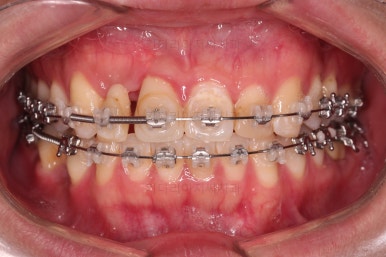

다행히 매복되었던 영구치는 잘 이동하였고요.

임플란트 자리도 적당한 크기로 점점 넓혀갑니다.

매복 영구치도 거의 다 배열되어 가고요.

임플란트 공간도 많이 확보되었습니다.

임플란트를 위한 기본 셋팅이 거의 완료되었습니다.

이 모습까지 13개월 걸렸네요.

굉장히 급한 마음으로 달려왔습니다.

지금부터는 임플란트, 보철 등을 진행하며 연산동치아교정은 보조적으로 진행하게 됩니다.